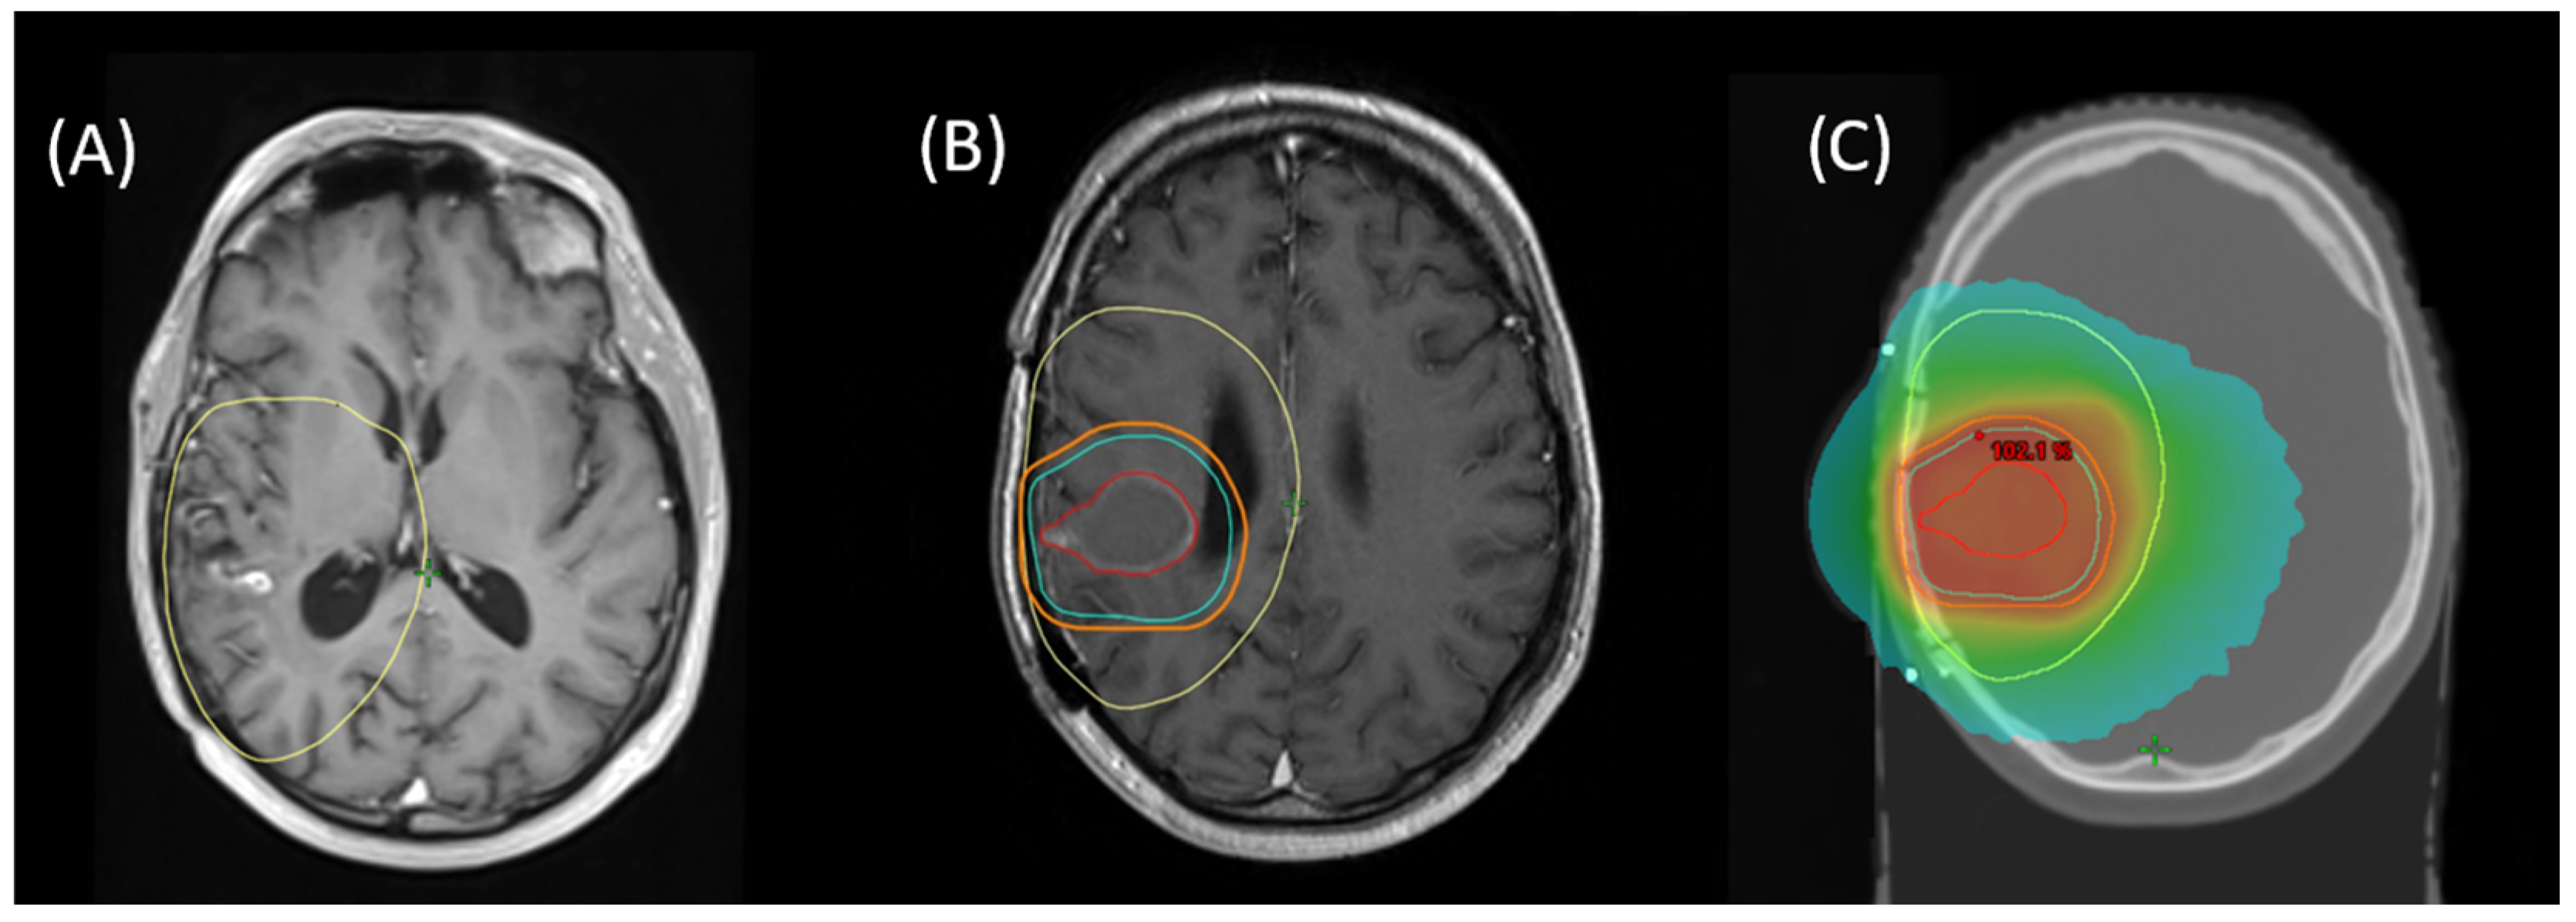

Re-RT planning was performed in accordance with ICRU8325. All patients were treated with 1.8–2 Gy daily fractions 5/week with IMRT-planning for conformal treatment volumes. All treatment plans and target volume definitions of patients included in this cohort were assessed. Treatment planning for all patients was realized via Varian Eclipse (by Varian medical systems, Palo Alto, CA, USA) or TomoTherapy® (by Accuray Inc., Sunnyvale, CA, USA). Diagnostic MRI was co-registered with the planning CT for all patients. Patients were treated with immobilization by a thermoplastic mask, using 6 MV or 15 MV Photons in different beam setups (Intensity Modulated Radiation Therapy [IMRT] or Volumetric Intensity Modulated Arc Therapy [VMAT], with helical therapy as a special form of VMAT). Re-RT target volumes were defined as standardized by ICRU50 with the gross tumor volume (GTV) enclosing the primary disease site (defined as sites of recurrent or progressing tumor after initial treatment, marked by blood–brain barrier disruptions in contrast-enhanced T1- and T2-MRI), the clinical target volume (CTV) incorporating sites of suspected subclinical infiltration (also considering the T2-FLAIR-signal if clinically appropriate), and the planning target volume (PTV) creating an additional margin to compensate for possible incongruences in patient positioning (usually 3–5 mm). For patients who received prior re-resection, the CTV was defined as areas of supposed residual tumor or associated with a high risk of subclinical infiltration, based on postoperative MRI (T2 and contrast-enhanced T1) with an additional margin, based on disease location and size, prior treatment, extent of resection, and clinical performance status. Postoperative patients with delayed initiation of radiation treatment (>3 weeks) received a dedicated planning MRI. An example for target volume definition and dose distribution is given in Figure 1.

Figure 1. Example for (A) MRI of recurrent blood–brain barrier disruption of the right temporal lobe as a manifestation of recurrent glioblastoma, fused with initial RT planning CT to show first-line treatment PTV (yellow). (B) Planning MRI after surgical resection for fusion with planning CT with resulting target volumes for re-RT (GTV = red, CTV = cyan, PTV = orange). (C) Resulting cumulative dose distribution for re-irradiation with 39.6 Gy via helical therapy.